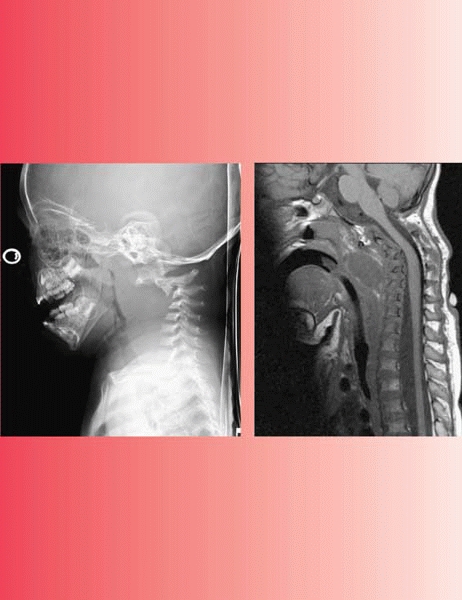

cervical instability, scoliosis, and spondylolisthesis. When evaluating

cervical spine instability, don’t just look at C1-C2, look at occiput

C1 as well (Fig. 13-1). A simplified and reasonable approach to cervical spine instability in Down syndrome is as follows:

▪ FIGURE 13-1

Be alert to the fact that the instability in the cervical spine of a child with Down syndrome can be at the occcipitocervical junction, not just C1-C2. Note the relatively normal flexion film (A), but the movement of the occiput on C1 with extension (B). |